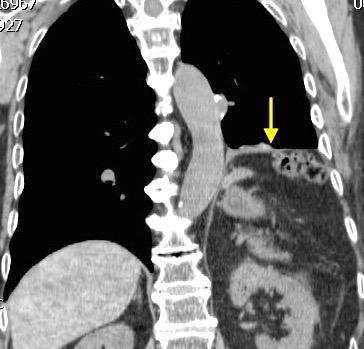

Parálisis frénica transitoria tras cirugía de válvula aórtica

Parálisis frénica transitoria post cirugía cardiaca (10%).

Puede acompañarse de atelectasia del LII.

Benjamin JJ et al. . Left lower lobe atelectasis and consolidation following cardiac surgery: the effect of topical cooling on the phrenic nerve. Radiology 1982